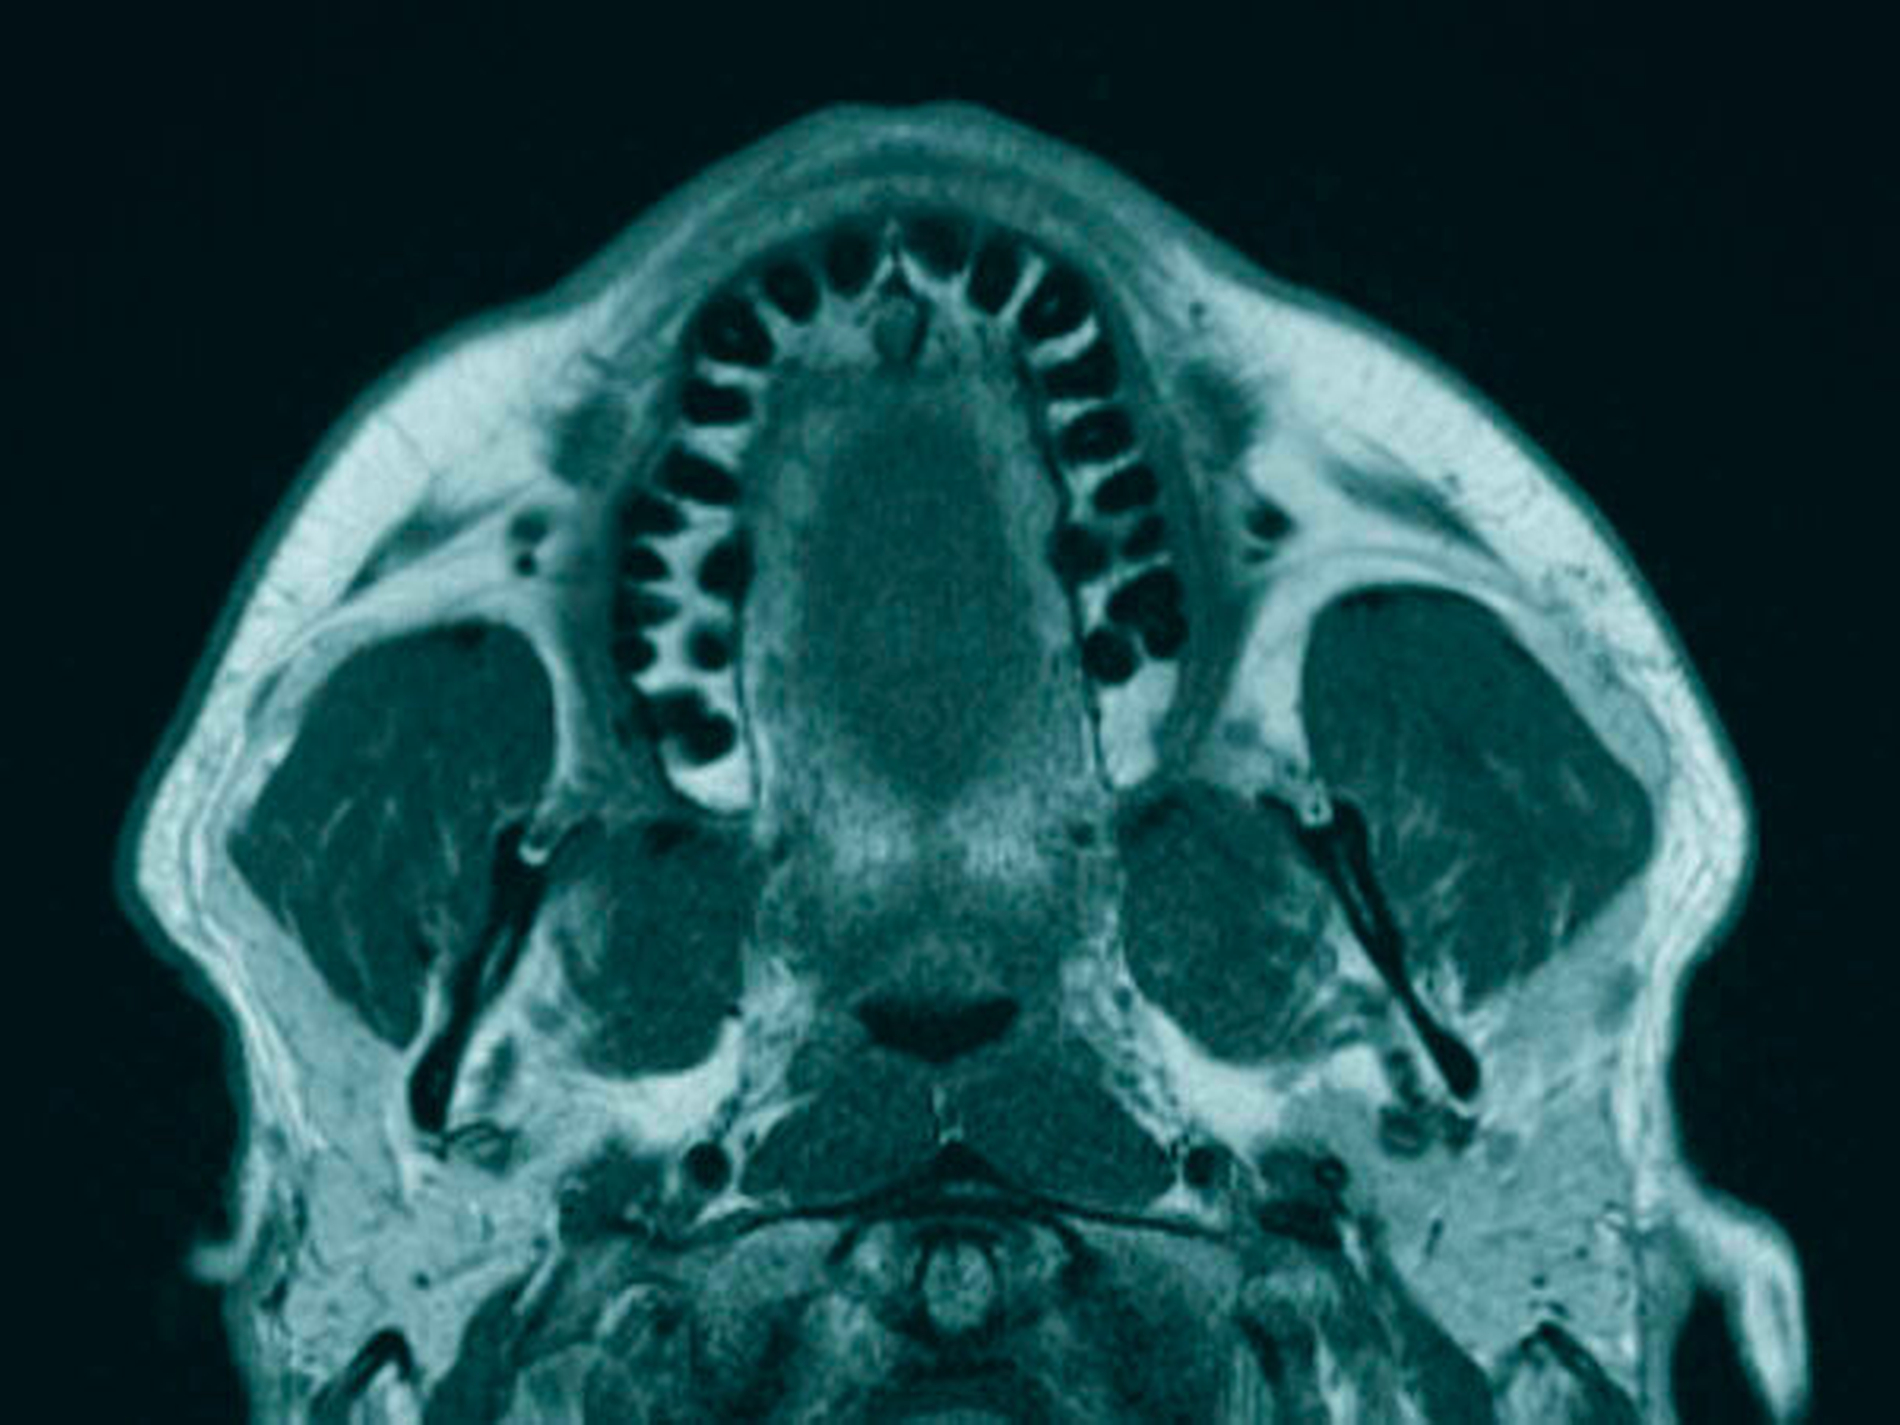

Anschließend wurde zur Ausbreitungsdiagnostik eine Magnetresonanztomografie (MRT) der Kopf-Hals-Weichteile mit Kontrastmittel durchgeführt (Abbildung 2). Hierbei kam eine malignomsuspekte Raumforderung im Oberkiefer im Bereich der regiones 11 bis 21 zur Darstellung, metastasensuspekte Auffälligkeiten der Halslymphknoten konnten nicht ausgemacht werden. Nach Besprechung des Falles in der interdisziplinären Tumorkonferenz wurde der Befund lokal mit Sicherheitsabstand in toto exzidiert und die mit der Raumforderung kommunizierenden Zähne 12, 11 und 21 extrahiert (Abbildung 3).